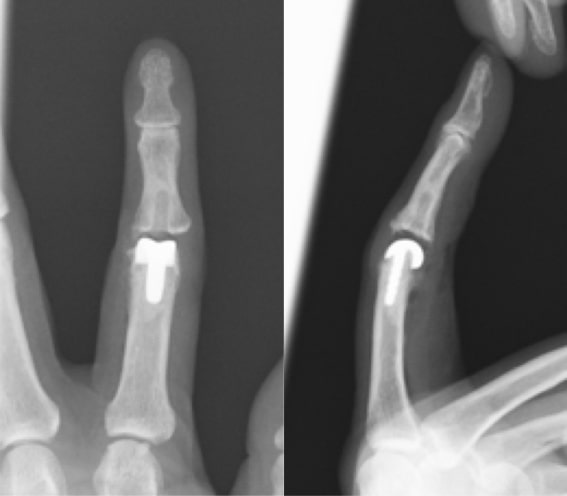

ブシャール結節

ブシャール結節写真1

ブシャール結節写真2

PIP関節の狭小化

ブシャール結節術後写真1

表面置換型人工指関節

ブシャール結節術後写真2

シリコン人工指関節

原因

第2関節(PIP関節)の変形性関節症。関節リウマチなどの膠原病でも腫れてくることがあるので鑑別が必要です。

症状

PIP関節がコブ状に膨らんで指が曲がって変形してきます。関節の痛みが強い場合も弱い場合もありますが、経過とともに、変形がすすみ関節が動かしにくくなります。どの指にも生じます。

治療方針

まずは、外用薬、テーピングなどの処方で様子をみます。痛みが強い場合には関節内注射をすることもあります。痛みが引かない場合や動かなくなり使い勝手が悪くなった場合は手術をします。手術は人工指関節置換術を行う場合が多いです。人工指関節には色々な種類があります。